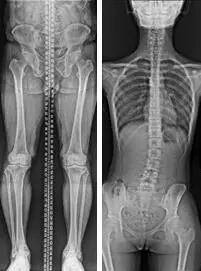

1.全脊柱拼接与长骨拼接,DRX-Compass X采用业内普遍认可的模拟“点光源”成像的最优拼接方式,在设置采集影像起止点后,一键控制即可完成机架的同步运行、依次曝光获取连续影像、全自动完成精确、安全的全景影像。